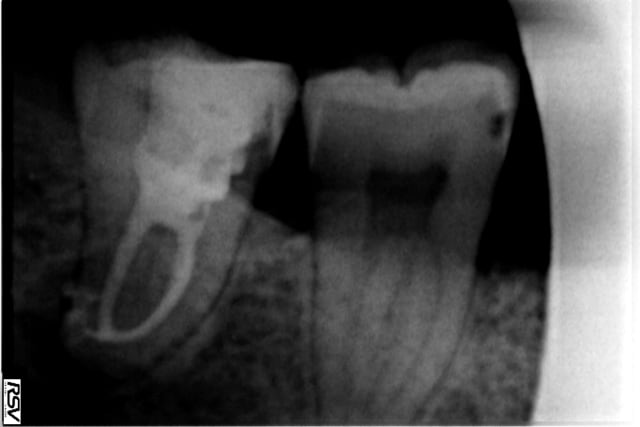

salut à toi, j'ai passé le orange direct à la LT quand j'étais dans la dent j'ai senti très peu de résistance honnêtement j'étais surpris par ma radio de contrôle et de la courbure. Ma radio préop était légèrement floue donc je n'avais pas anticipé la courbure.

J'ai fait 4 bio molaires avec la même lime avant de la jeter, sur deux de la douzaine des canaux que j'ai traité avec j'ai eu deux canaux mésiaux sur lesquels cela a commencé à "forcer" légèrement donc j'ai passé ma séquence de revo s(que j 'avais à portée de main)pour passer la contrainte.

Je n'ai pas commandé de jaune en fait mais j'ai traité quelques prémolaires très fines et avec des apex en s avec les rouge c 'est passé sans problème.